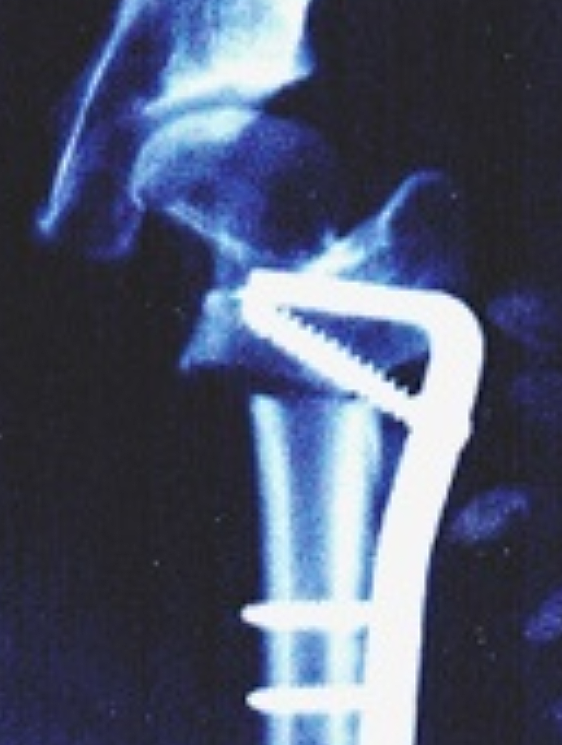

고관절 통증 증상은 조기에 발견하고 치료받는 것이 무엇보다 중요합니다. 고관절 손상이 심하지 않고 통증이 가볍다면 약물치료와 운동치료 등 보존적 치료를 통해 회복할 수 있습니다. 하지만 고관절 손상이 심하고 일상생활에 지장을 줄 만큼의 심한 고관절 통증 증상이 있는 경우라면 괴사된 관절을 제거하고 인공관절을 삽입하는 고관절의 인공관절 치환술을 해야 합니다.